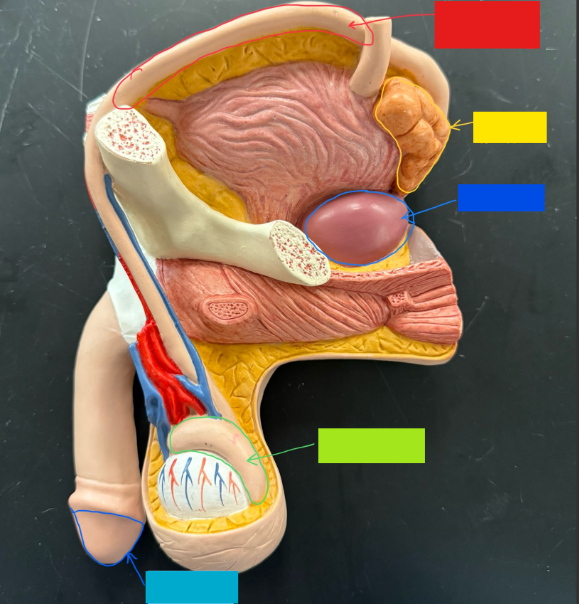

What is the name of the blue box?

Corpus spongiosum

What is the name of the light green box?

Glans penis

What is the name of the red box?

Seminiferous tubules

What is the name of the black box? X2

Prostate